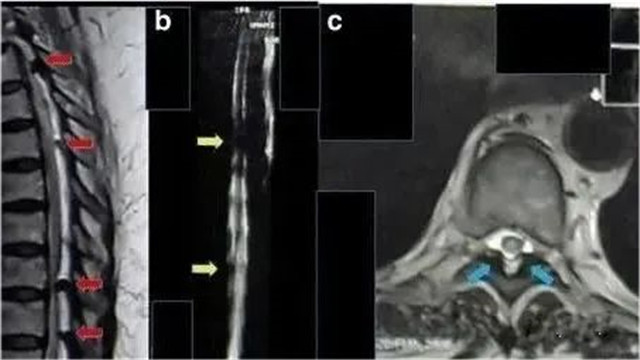

2017年(nián)海(hǎi)外(wài)報(bà"✘σo)道(dào)一(yī)例62歲的(de)印尼籍婦女(nǚ),被診斷為(£×wèi)胸部截癱、慢(màn)性腎功能(néng)衰竭、糖尿病,長(cháng$→)期腎髒受累,慢(màn)性腎功能(néng)衰竭2年(nián)αε≠α,肌酐水(shuǐ)平為(wèi)11m¥≥g/dL,無小(xiǎo)便。

采用(yòng)間(jiān)充質幹細胞¶&移植方案治療。鞘內(nèi)注射1.6×10^7個(gè)間(jiān)充質幹細胞,靜(→ jìng)脈注射1.6×10^7個(gè)間(jiān≤☆Ω)充質幹細胞。

△ 患者胸部磁共振成像顯示,脊髓受到(dào)多(duō)處 α↕壓迫

鞘內(nèi)注射和(hé)靜(jìng)脈注射後三周後₽↕γ,患者可(kě)以移動腳趾,腎功能(néng)得(de)到(dào)改善。肌酐水(shuǐ)αε®平降至9 mg/dL。8個(gè)月(yuè)後,患者可(kě)以擡起腿,肌酐水(shuǐ)平是σ↕Ωσ(shì)2mg/dL,小(xiǎo)便恢複正常。